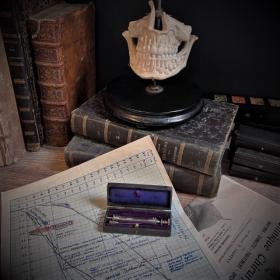

"Tarnier" Forceps - COLLIN: french manufacturer of surgical instruments

Antique glass urethral syringe by Dr JANET

For injection of liquid into the urethra

Antique glass urethral syringe by Dr JANET

For injection of liquid into the urethra

Pharmacopée royale galénique et chymique - 1753

Antique and Illustrated Pharmacopoeia

By Moyse CHARAS

This book contains all the plants, minerals and animals that went to make up the remedies used in those days. Some of them are quite surprising to our modern eyes.